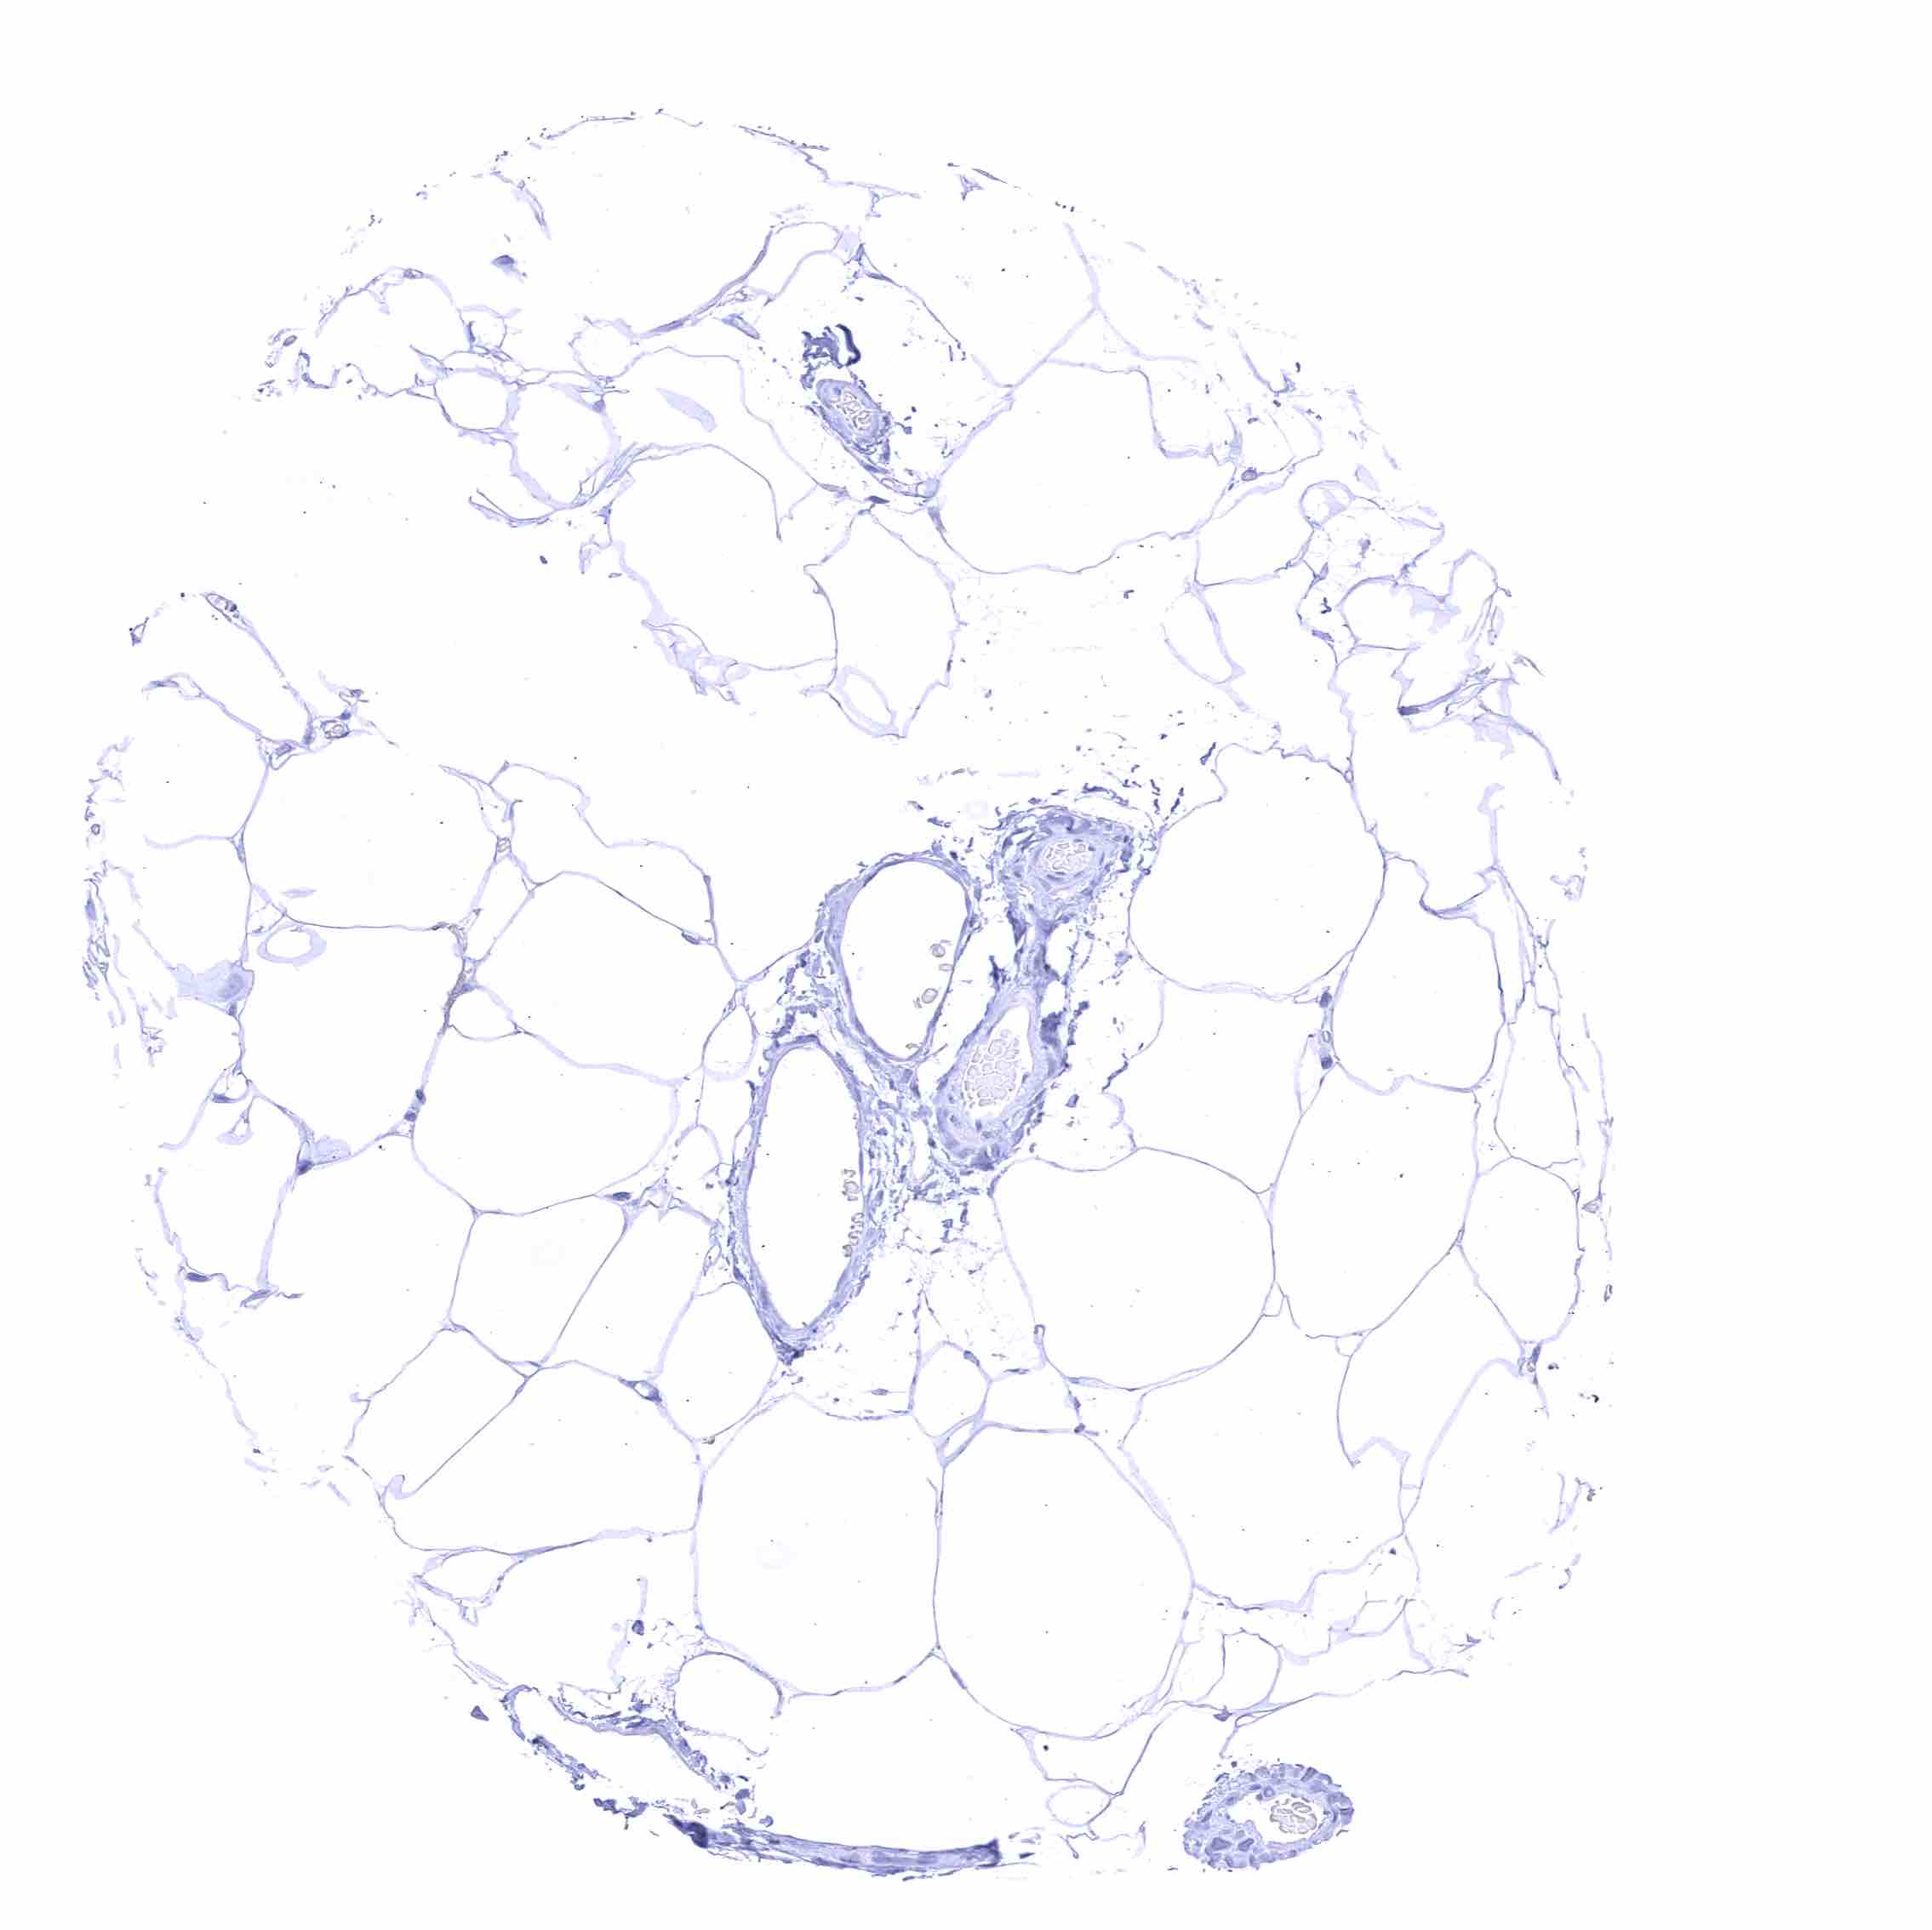

Fat